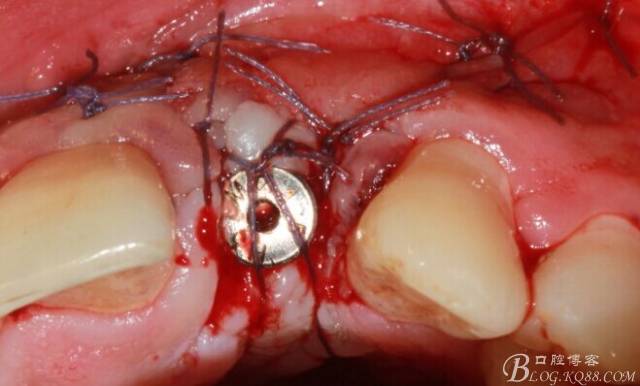

縫合。

4個(gè)月后,唇側(cè)豐滿度尚可,與鄰牙之間齦乳頭完整。